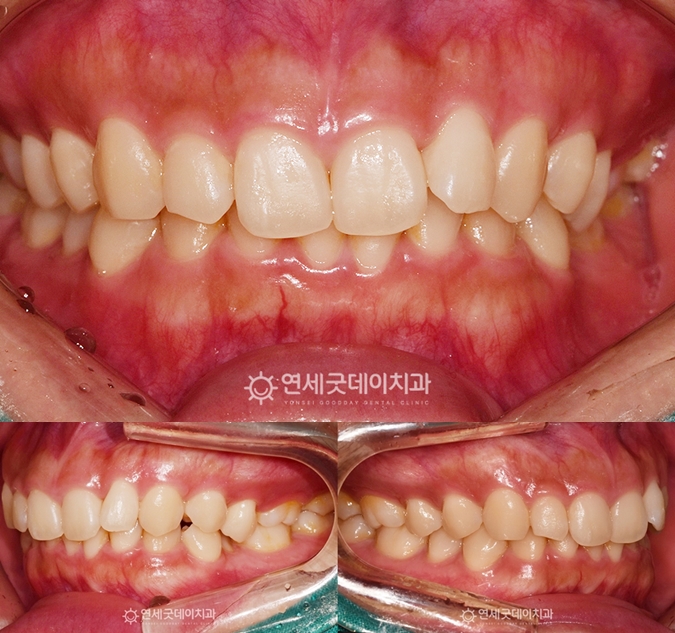

하지만 #35 치아가 쓰러지면서 또 한 가지 주의 깊게 살펴볼 부분은 ‘과개교합’입니다. ▲ 치료전 안모 (촬영시기 : 2022년 10월) 환자분은 과개교합, 쓰러진 치아로 인한 인접치의 정출 따라서 부분교정의 한계점에 대해 충분히 설명드린 후 ▲ 과개교합 교정 후 엑스레이 (촬영시기 : 2024년 3월) 약 1년 6개월의 인비절라인 교정이 마무리되었습니다. 기울어진 치아는 정상적인 위치로 올바르게 세워졌으며 ▲ 과개교합 교정 종결 (촬영시기 : 2024년 3월) 윗니의 높이와 각도가 개선되면서 아랫니가 정상적으로 드러나고, ▲ 치료 후 안모 (촬영시기 : 2024년 3월) 웃을 때마다 과도하게 드러났던 거미스마일도 ▲ 치료전후 비교 (촬영시기 : 2022년 10월 / 2024년 3월) 과개교합은 턱관절 불편감이나 저작 불편으로 이어질 수 있어 과개교합을 교정함으로써 증상을 완화하고 그동안 치료 받으시느라 고생 많으셨습니다. ^^ ※ 모든 사진은 본인의 동의를 얻어 동일조건에서 촬영하였으며 |